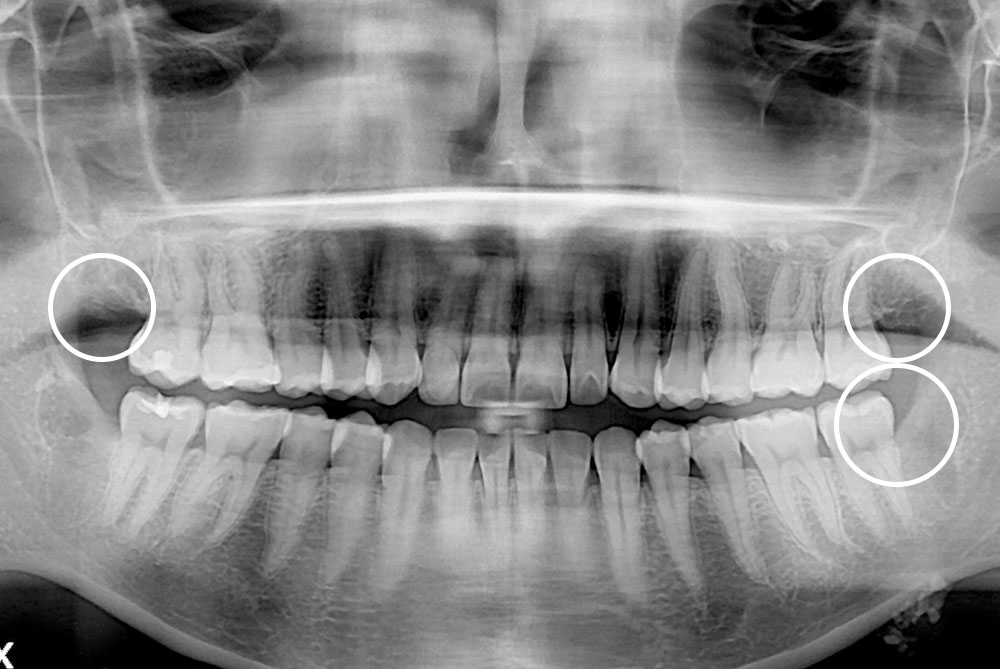

[사랑니] 매복 사랑니 발치

치료후 : 2020-07-08

세종치과는 구강악안면외과학 박사이신 원장님이 발치하는 치과입니다.